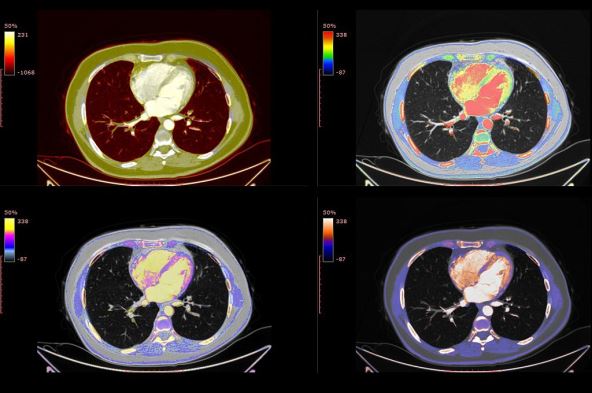

Međutim, kliničari otkrivaju da i - pre nalaza PCR testa - CT snimak može da ukaže na prisustvo korona virusa u organizmu.

Međutim, kad bismo im uradili CT skener  stomaka, uhvatili bismo i donji deopluća a na snimku smo otkrili zamućenja u karakterističnom okruglom obliku i boji mlečnog stakla. kaže dr Bernhajm.

Ova zamagljenja razlikuju se od oštećenja kakve izaziva, recimo, karcinom pluća kao i od posledica zaraze korona virusom sa teškim respiratornim tegobama.

Drugim rečima, ako postoji sumnja na COVID-19 zbog zaraženih kontakata a nema karakterističnih simptoma, CT slika može da pruži važne podatke lekarima.

Sa druge strane, nalaz "mlečnog stakla" na plućima treba da bude i upozorenje za pacijente da treba da budu veoma oprezni čak i ako nemaju druge simptome.